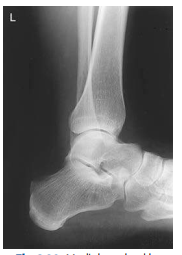

What ankle view is this?

Oblique